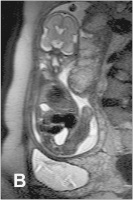

Fetus - 32. SSW

Abbildung 4: Fetus in der 32. SSW mit linksseitiger kongenitaler Zwerchfellhernie, koronale Schichtführung. Mit Hilfe der hier verwendeten Kontrastparameter können intrathorakal mit Mekonium gefüllte Darmanteile sehr hell dargestellt werden. Die Leber, sie ist etwas weniger hell als Mekonium, liegt intraabdominal. Am Hals ist auch die Glandula thyroidea zu erkennen.